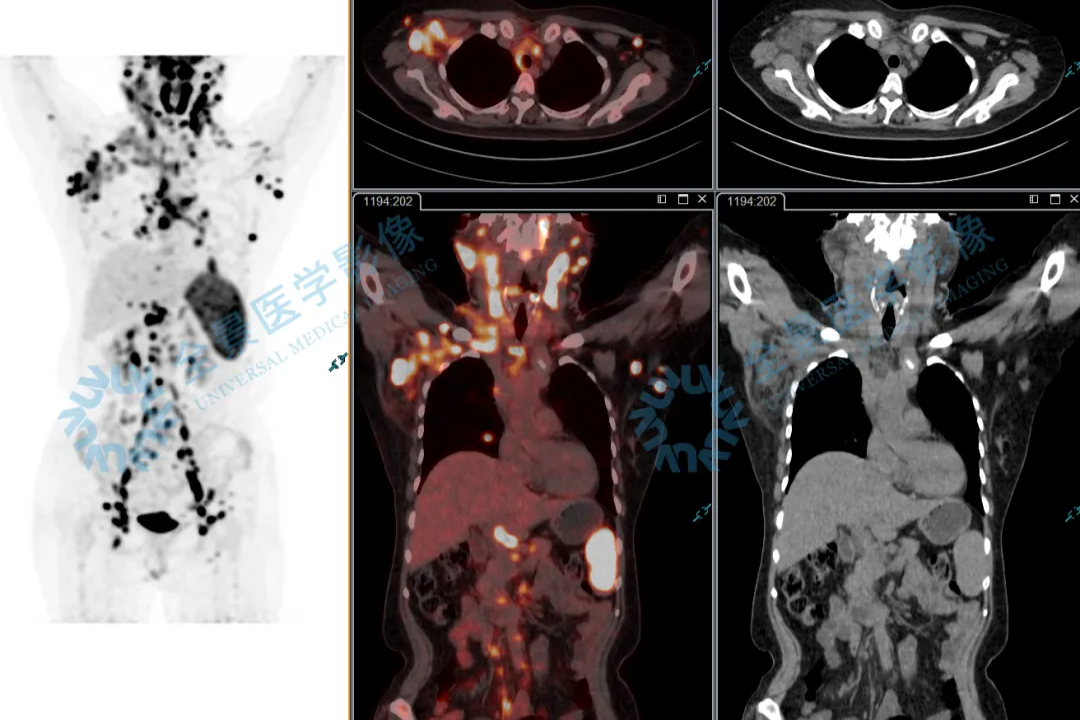

淋巴瘤治疗显成效!PET/CT 见证病灶「大撤退」

淋巴瘤治疗显成效!PET/CT 见证病灶 「大撤退」